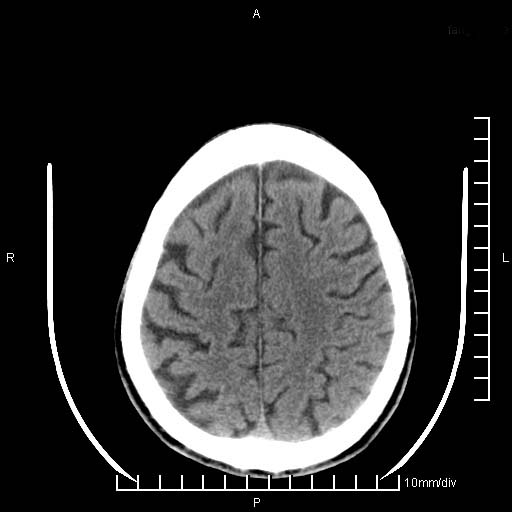

临床以双下肢浮肿,疼痛收治,无明显神经系统症状,既往无梗塞,出血病史。左颞叶见低密度灶,考虑什么?

考虑左侧颞叶脑软化灶。

无强化 无占位 软化灶吧

无强化、 无占位、局部脑沟增宽, 软化灶吧。